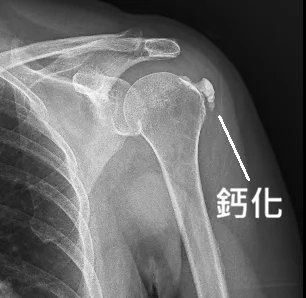

打了幾十次震波都沒用?50歲大姐的肩膀「頑石」消除記—超音波導引鈣化沖洗術

一位飽受肩膀劇痛折磨的50歲女性,歷經數月、數十次震波治療無效,生活幾近停擺。來到宸新後,透過高階超音波揪出導致疼痛的「頑固鈣化結石」。在嘗試高能量震波仍未改善後,醫師果斷採取「超音波導引鈣化沖洗術」,直接將肌腱內的結石「洗」出來,兩週後重獲新生。